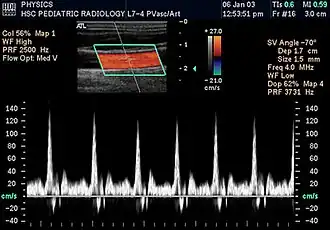

Doppler ultrasonography is medical ultrasonography that employs the Doppler effect to perform imaging of the movement of tissues and body fluids (usually blood),[1][2] and their relative velocity to the probe. By calculating the frequency shift of a particular sample volume, for example, flow in an artery or a jet of blood flow over a heart valve, its speed and direction can be determined and visualized.

Duplex ultrasonography sometimes refers to Doppler ultrasonography or spectral Doppler ultrasonography.[3] Doppler ultrasonography consists of two components: brightness mode (B-mode) showing anatomy of the organs, and Doppler mode (showing blood flow) superimposed on the B-mode. Meanwhile, spectral Doppler ultrasonography consists of three components: B-mode, Doppler mode, and spectral waveform displayed at the lower half of the image. Therefore, "duplex ultrasonography" is a misnomer for spectral Doppler ultrasonography, and more exact name should be "triplex ultrasonography".[3]

Colour Doppler shows the direction of the blood flow in red or blue (either towards or away from the transducer). Meanwhile, spectral Doppler not only shows the direction of blood flow, it also shows the phases (pulsatility) and acceleration of the blood flow. Any sudden changes in direction of blood flow produces audible sounds on the ultrasound machine.[3]

In spectral Doppler, the y-axis shows the direction and velocity of the flow. Meanwhile, the x-axis (as known as "baseline") shows the flow over time. The gradient at any point on the waveform would therefore shows the acceleration of the flow. In "antegrade" flow, the blood flows according to the normal flow within the circulatory system (e.g. veins flow towards the heart while arteries flows away from the heart). In "retrograde" flow, the flow would reverse (e.g. veins flow away from heart or arteries flow towards the heart). However, "retrograde" flow can be both abnormal or normal. For example, in portal hypertension, there is an abnormal portal venous flow where it flows away from the liver (hepatofugal flow) instead of the normal flow towards liver (hepatopetal flow). In jugular venous pressure waveform of the internal jugular vein, the retrograde "a" waveform is a normal flow due to right atrium contraction. Both antegrade or retrograde flow can be either towards or away from the probe transducer, depending on the position of the probe relative to the blood flow. Blood flow toward the transducer would appear above the baseline while blood flows away from the transducer will appear below the baseline. Waveform of the flow can be classified as: pulsatile (as in arteries), phasic (as in veins), non-phasic (as in diseased veins), and aphasic (no flow). Spectral broadening (thickness of the waveform) increases from large vessels (plug flow) to medium vessels (laminar flow) to small/stenotic/diseased vessels (turbulent flow) due to a larger variety of blood with different ranges of velocities in those with turbulent flow.[3]